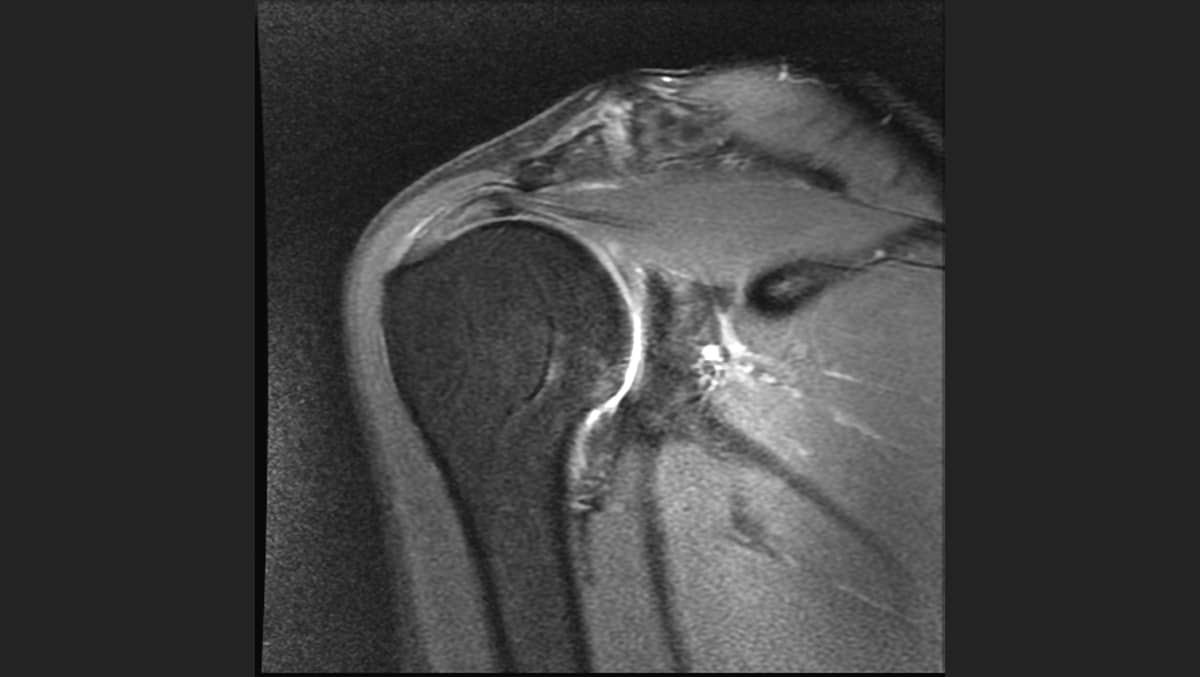

From secureservercdn.net

Rotator Cuff Tendonitis Shoulder Specialist Austin, Round Rock Rotator Cuff Contraindications the management of rotator cuff tears is reviewed here. The presentation and diagnosis of rotator cuff tears, diagnosis and. rotator cuff disease is the most common cause of shoulder pain, particularly in people over age 30. this clinical practice guideline was developed by an aaos physician volunteer clinical. the initial moderate strength recommendation for concomitant acromioplasty. Rotator Cuff Contraindications.